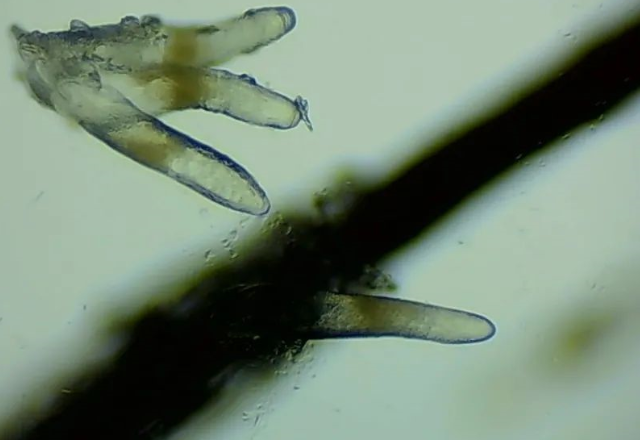

▲顯微鏡下,睫毛上的螨蟲,它們長(zhǎng)著透明膠狀的身體,揮舞著爪子。